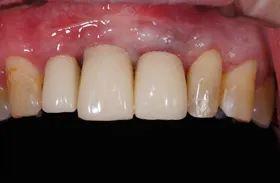

金属を白くし、歯茎の黒ズミを改善したケース

■治療前

■治療後

| 主訴 | 全体的に白い歯にして見た目をきれいにしたい 歯茎が黒くなっているのが気になる、歯ならびも良くしたい |

| 治療方法 | 矯正治療+歯茎の黒ずみの改善+補綴治療 |

| 治療期間 | 3年 |

| 通院回数等 | 約40回 |

| 費用 | 約350万円 |

| リスク・副作用 | 矯正治療も行ったので治療期間が長くなった |